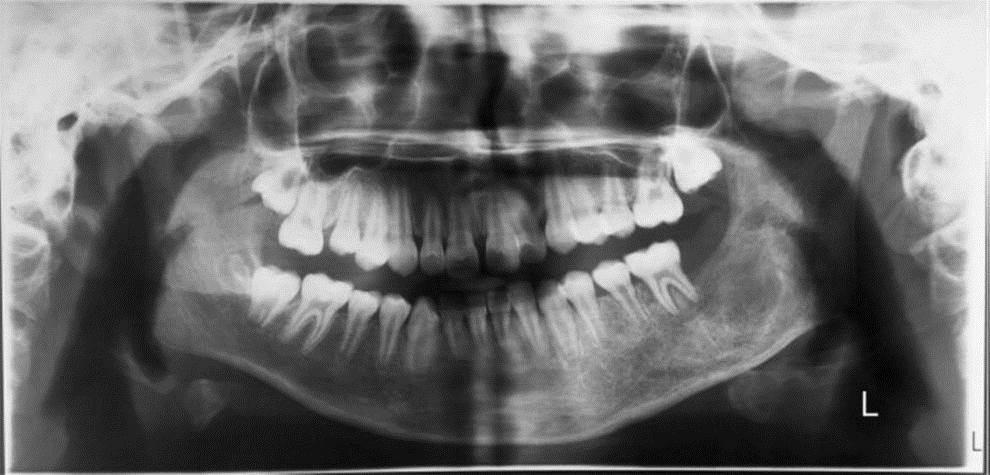

Radiográficamente, las malformaciones vasculares de las mandíbulas se han denominado «grandes imitadoras radiológicas» y pueden parecerse a cualquier lesión, desde un quiste hasta una neoplasia maligna. En la mandíbula, la malformación vascular produce una imagen radiotransparente mal definida, a menudo con apariencia de panal de abejas o burbujas de jabón, con pequeñas lagunas redondeadas y desiguales o un área perforada. Las MAV aparecen con mayor frecuencia como radiotransparencias multiloculares en exámenes panorámicos con canal alveolar inferior dilatado y ensanchamiento de los espacios medulares. Por lo tanto, se debe considerar un gran número de tumores, tanto benignos como malignos, en el diagnóstico diferencial. De las lesiones benignas, los quistes escamosos son los más frecuentes. Las lesiones menos comunes incluyen los quistes no epiteliales (también conocidos como quistes óseos hemorrágicos o traumáticos), la displasia fibrosa, el fibroma, el mixoma, el neurofibroma, el granuloma eosinofílico y los quistes óseos aneurismáticos. Dado que suele aparecer como una radiotransparencia multilocular, se considera que otras técnicas radiográficas, como la TC, la RM y la angiografía por sustracción digital (ASD), permiten obtener un diagnóstico preciso de la MAV.